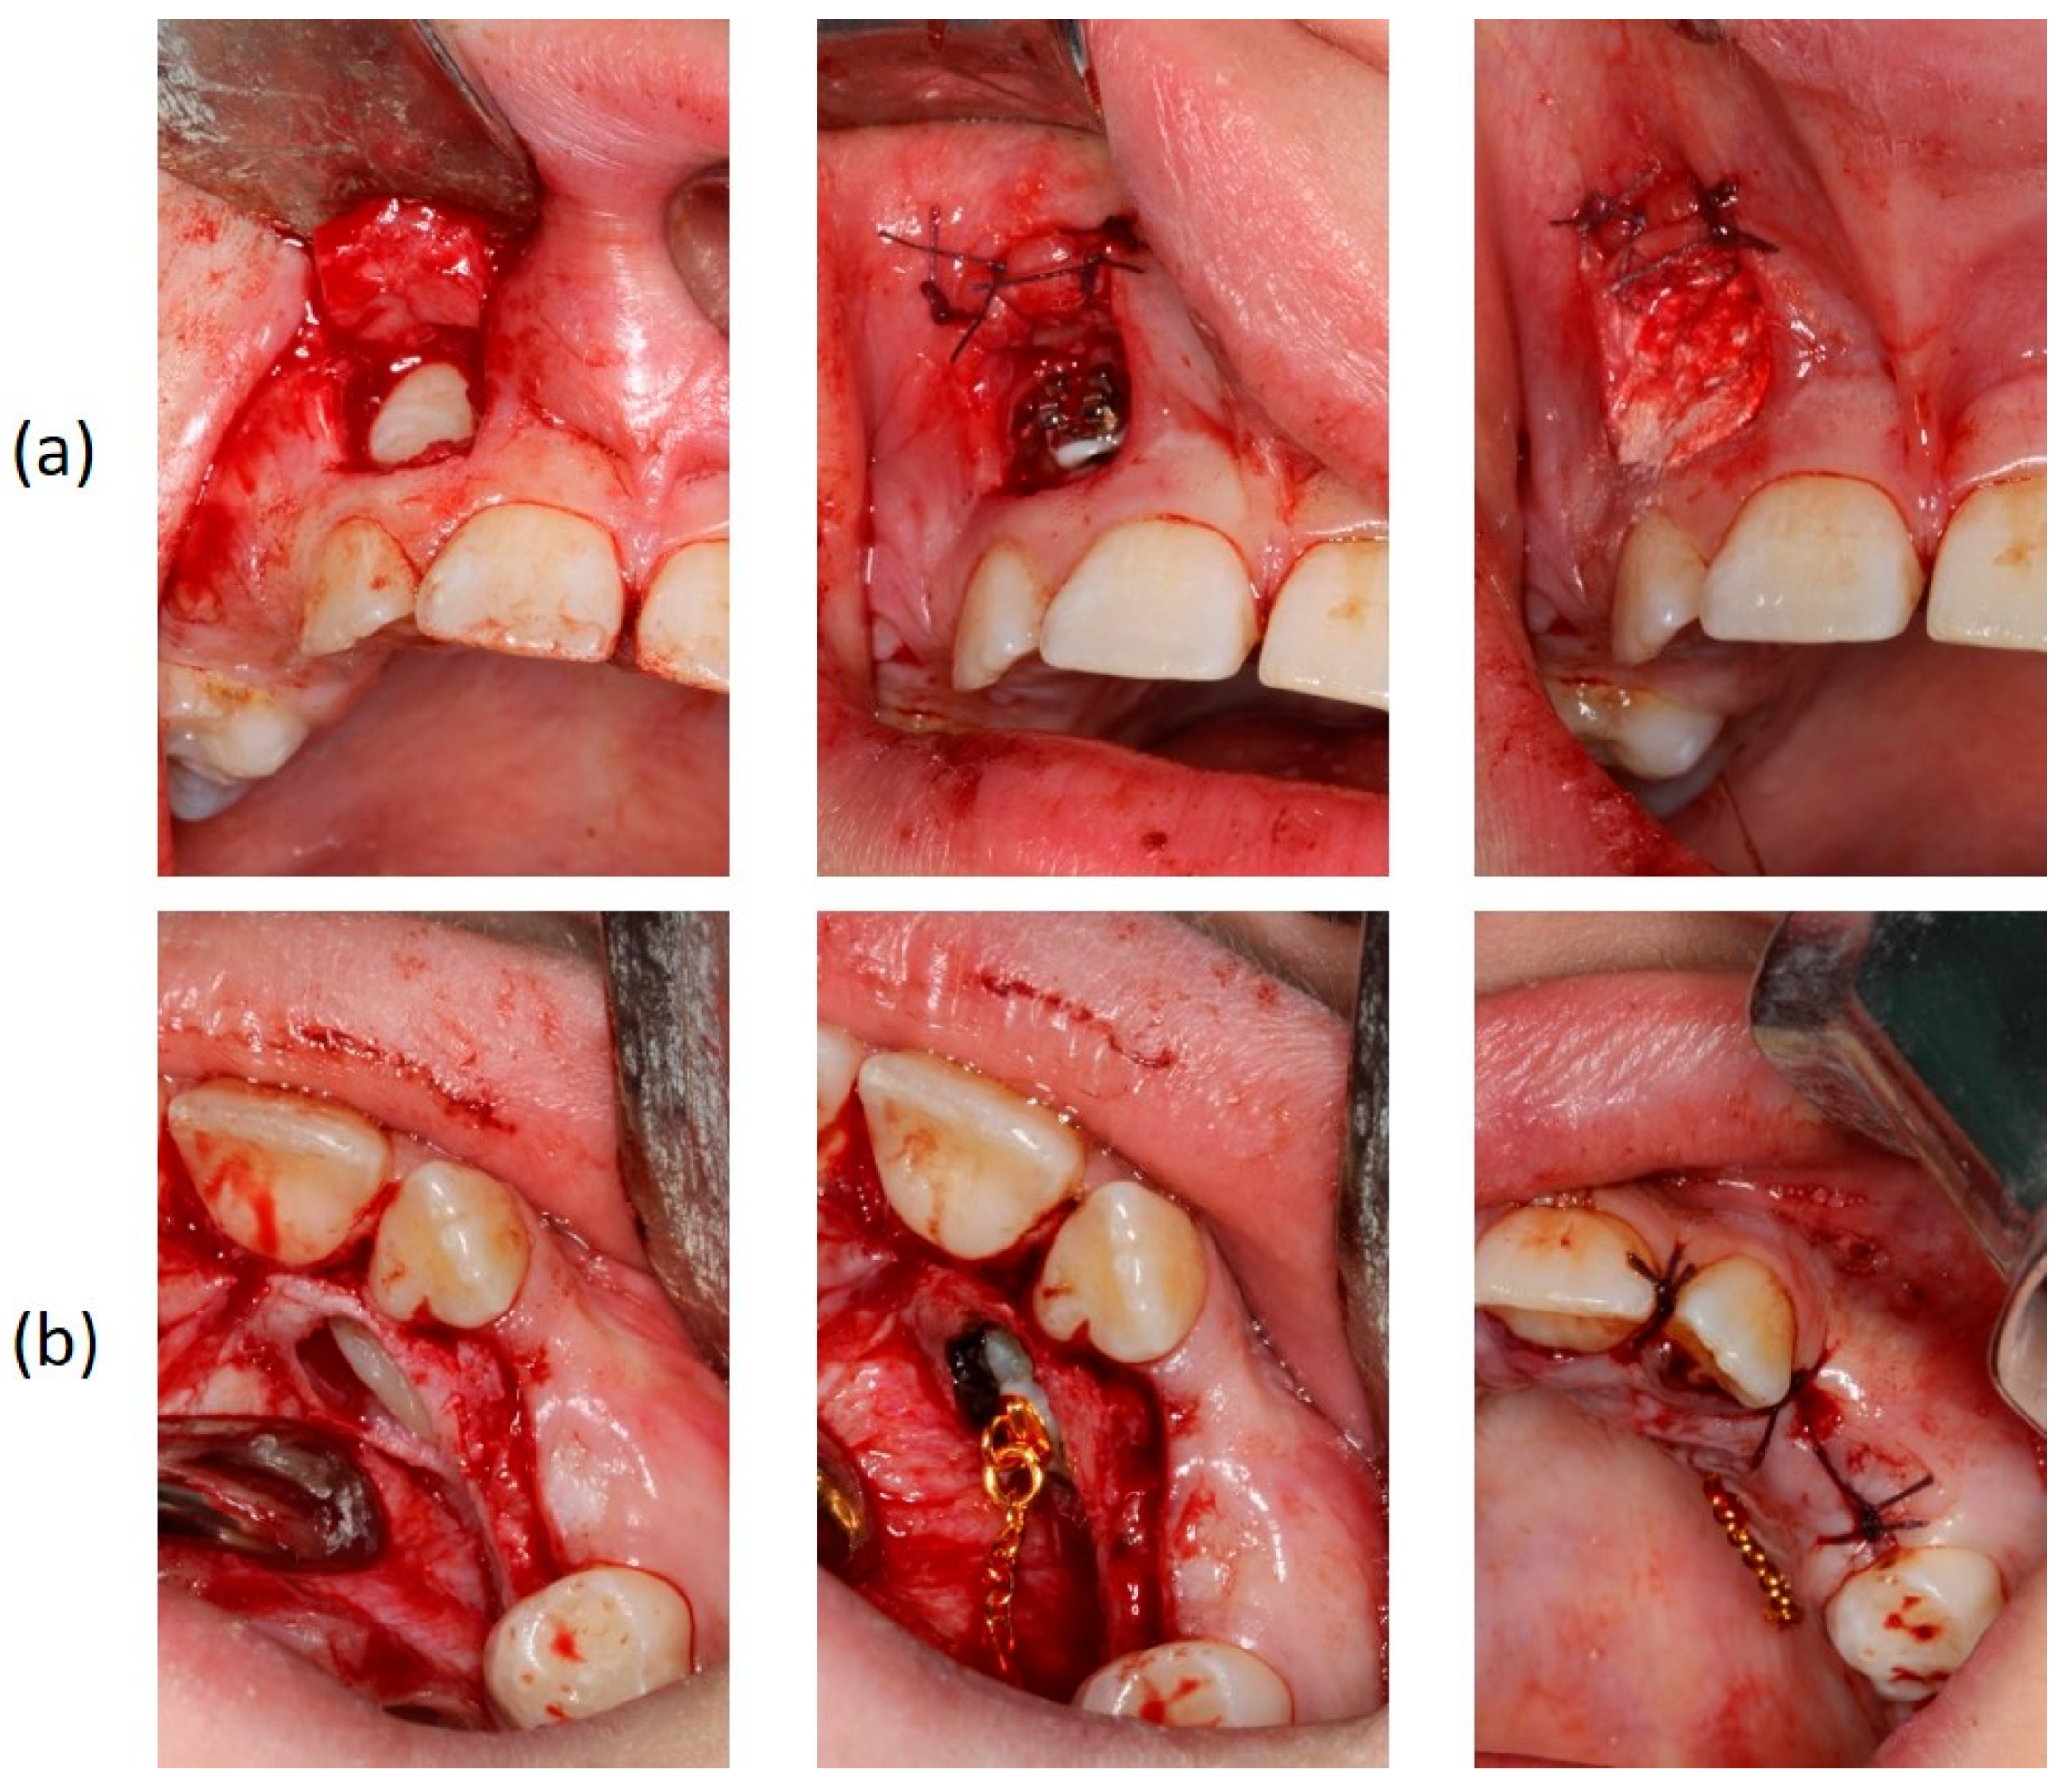

Figure 5.

Surgical exposure of the upper right (a) and left impacted canines (b).

The orthodontic treatment was initiated with the canine exposure (Figure 5) and traction with light forces using a custom-made trans-palatal arch for anchorage purposes (Figure 6 and Figure 7). An open surgical technique (apically positioned flap) was used to expose the labially positioned right canine and a closed technique for the left, which was positioned palatally. Sectional mechanics were applied during treatment until the eruption of all permanent teeth (Figure 8). The upper lateral incisors were extracted after the successful eruption of the impacted canines and for aesthetic reasons. Subsequently, comprehensive orthodontic treatment was performed using fixed 0.018-inch-slot edgewise appliances. A lower lingual arch was placed to preserve the leeway space thus helping with the lower crowing. The progression of the archwire sequence was from 0.014-inch nickel-titanium to 0.016-inch Australian archwires. Class III light elastic forces were used bilaterally to help with space closure on the upper arch.